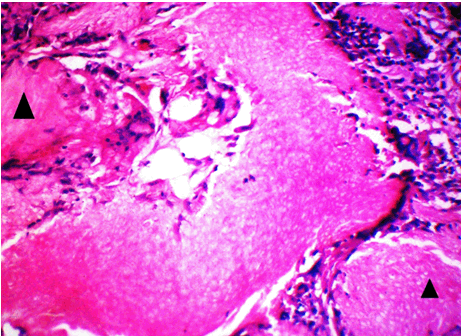

The clinical diagnosis in all the cases was suggestive of epidermoid/dermoid cyst. However, subsequent histopathologic examination confirmed these cases as pilomatricoma. All the lesions were well encapsulated. H&E sections showed dual population of cells comprising the peripheral basaloid cells and the ghost or shadow cells in the centre (Figure 1). A transition of basaloid to ghost cells was noted in many areas. Sections from the right eyebrow swelling posed great difficulty in diagnosis since there were mainly ghost cells present and almost negligible basophilic cells representing stage 4 (Figure 2). The remaining four cases (80%) belonged to the third morphological stage. Two cases showed a rich infiltrate of lymphoplasmacytic cells and numerous foreign body giant cells near the shadow cells (Figure 3). Three cases showed areas of calcification.

Figure 3: Photomicrograph showing rich lymphoplasmacytic cell infiltration and numerous foreign body giant cells (↑) (H&E stain, x400).